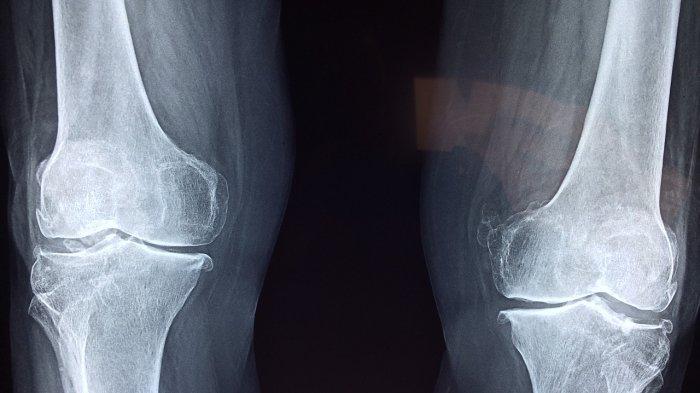

Baca juga: Kenali Beberapa Gejala Osteoarthitis yang dapat Mempengaruhi Sendi dan Kerusakan Tulang Rawan

- osteoartritis